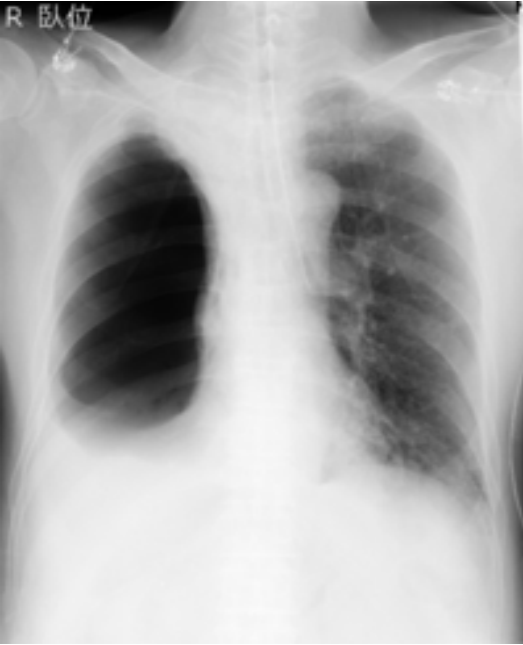

0.13–0.18ug/kg/min。插管后立即开始单肺通气,并在整个手术过程中持续进行。整个手术过程中外周血氧饱和度为98-99%。拔管前的胸片显示右侧胸腔透光度高(图3)。

图3. 胸片显示右侧胸腔透光度高

医生怀疑肺大泡破裂导致气胸;但是,由于血流动力学和呼吸状态稳定,未置入胸腔引流管